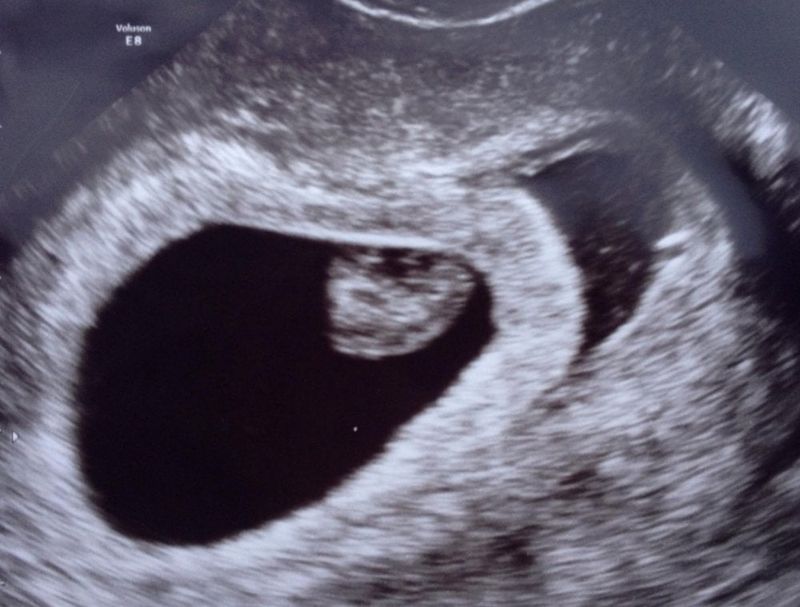

Er werd ons aangeraden om even één maand mijn lichaam rust te geven en daarna mochten we het in principe weer proberen. En ja hoor, die eerste poging was het gewoon alweer raak! In september 2015 was ik opnieuw zwanger. Maar dit keer voelde ik geen blijdschap. Ik voelde me schuldig naar het kindje en ik durfde gewoon niet meer. De eerste echo met zes weken was goed. Een mooi kloppend hartje, maar wel 2-3 dagen minder ver dan gedacht. Dit zat me niet lekker, maar vol goede moed gingen we naar de volgende echo een week later. Hier bleek het kindje amper gegroeid te zijn. Net iets meer dan zes weken, terwijl ik ruim zeven weken moest zijn. Maar nog steeds een mooi kloppend hartje en een goed vruchtzakje. Toch voelde het niet goed en ik zei tegen mijn man die avond, dat als deze zwangerschap ook fout moet gaan, dat ik dan liever heb dat het meteen fout gaat en niet pas bij de termijnecho of zelfs pas met bijna 39 weken. En alsof de natuur me gehoord had, diezelfde avond begon ik bloed te verliezen. Niet veel, maar voldoende om te weten dat het klaar was. De volgende ochtend in het ziekenhuis bleek ik het vruchtje al verloren te zijn. Weer een regenboogje dat niet mocht blijven…